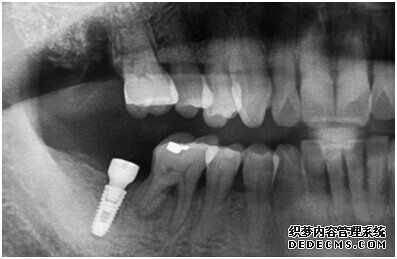

种植设备检查牙齿

成功植入种植体后的效果图

种植体成功植入后的CT效果图